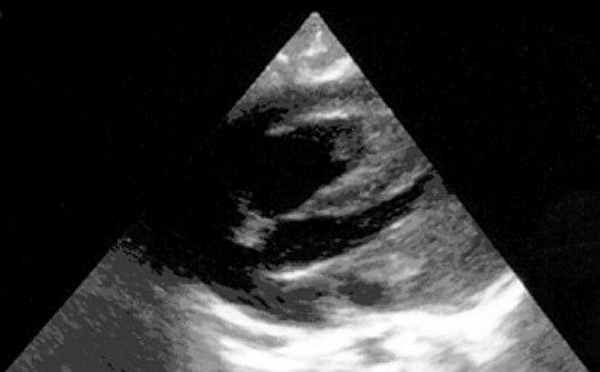

3 тип -большие пролабирующие миксомы. Двухмерная эхокардиография выявляет множественные левопредсердные сигналы, которые поступают в левый желудочек во время диастолы и вызывают нарушения движения клапана в диастолу (рис.156).

Миксома левого

предсердия,

пролабирующая

в левый желудочек.